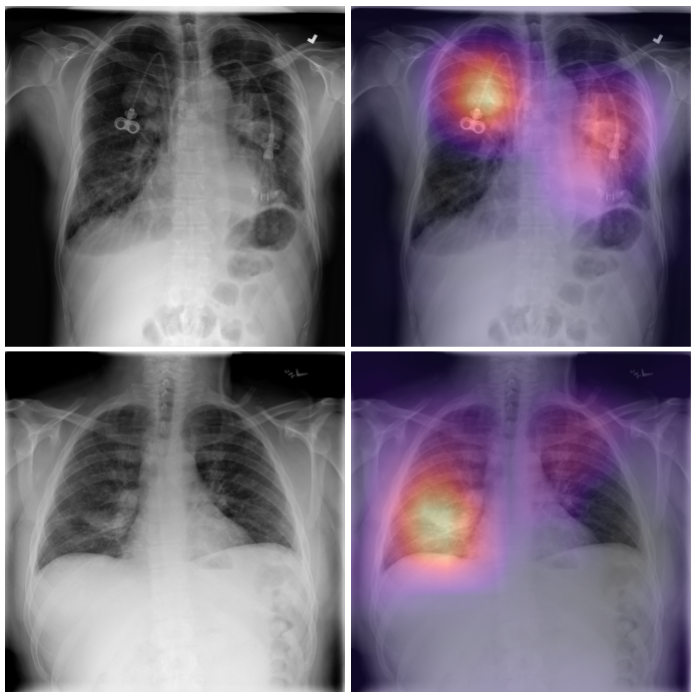

Grad-CAM? I would like the image after classification to return withclass activation mappingas shown in the image, to actually show where the CNN is looking,Can i add theGrad-CAMfunctionality to the model or as an independent function inapp.js?